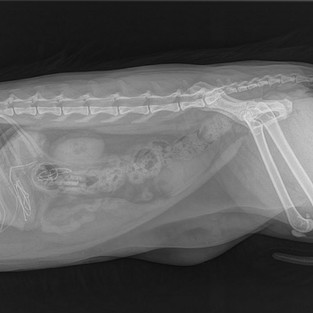

Gyomorból eltávolított műanyag játék egy darabja, bélből eltávolított műanyag kupak, a röntgen képen pedig lenyelt fülhallgató zsinórja a gyomorban